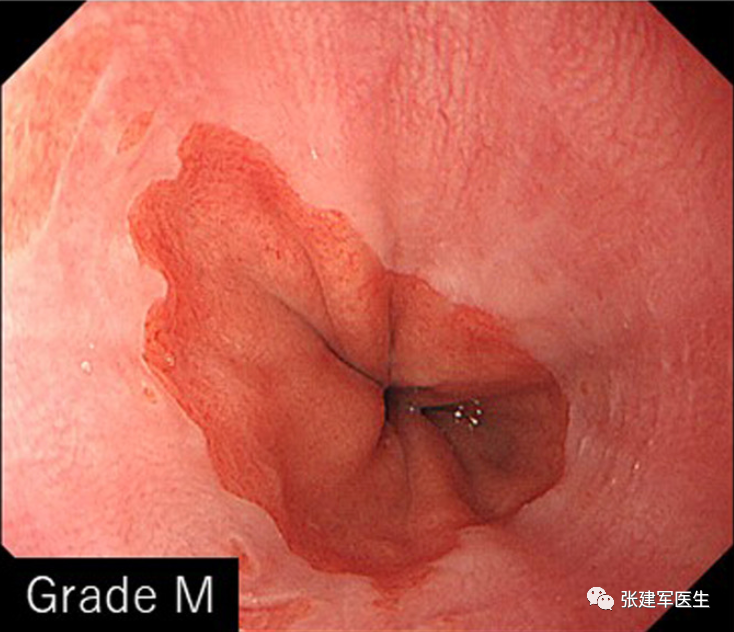

胃十二指肠镜检查

能直观评估食管、胃以及十二指肠粘膜状态,诊断糜烂性食管炎及巴雷特食管(Barrett's esophagus),明确食管裂孔疝的大小及类型,确定食管裂孔疝有无扭转。